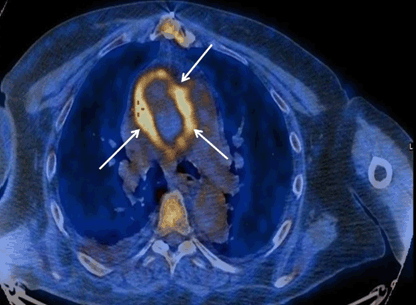

CASE REPORT Open Access Usefulness of 18 F-FDG-PET/CT in aortic graft infection: two cases Eiki Tayama*, Hidetsugu Hori, Tomohiro Ueda, Takanori Kono, Ken-ichi Imasaka, Takeaki Harada and Yukihiro Tomita ... Access This Document